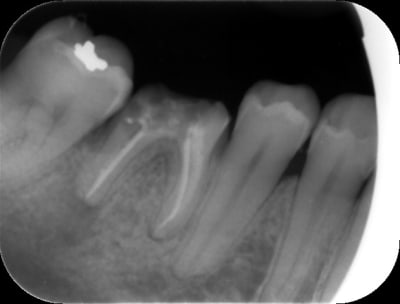

Regardez là j'ai fait faire un scanner en sachant à l'avance que ça ne servirait à rien ...

Résultat : irradiation inutile, supplément pour la patiente etc etc

Et des comme ça on en a tous régulièrement